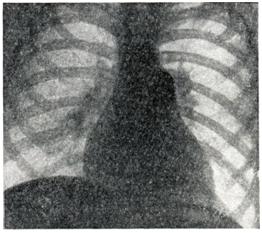

Рис. 1. | ||

Рентгенологические признаки зависят от характера бронхо-легочного заболевания, а при его отсутствии соответствуют картине первичной легочной гипертензии. При рентгеноскопии видна усиленная пульсация легочного ствола и крупных ветвей легочной артерии и, как и на рентгенограммах (рис. 1.), определяются выбухание дуги легочного ствола, увеличение калибра артерий в корнях и прикорневых зонах легких, «ампутация» теней сегментарных сосудов и отсутствие легочного рисунка в периферических отделах легочных полей. В правом переднем косом положении отмечаются выбухание легочного конуса и увеличение диаметра круглой тени левой легочной артерии в ортогональной ее проекции. В левом переднем косом положении «аортальное окно» закрыто тенью расширенного легочного ствола; обычно, как и в боковом положении, имеются признаки увеличения правого желудочка.

Углубленное рентгенологическое исследование (томография, электрокимография, ангиокардиография) выявляет при Айерсы синдроме расширение только артериальных сосудов, в то время как легочные вены не расширены.